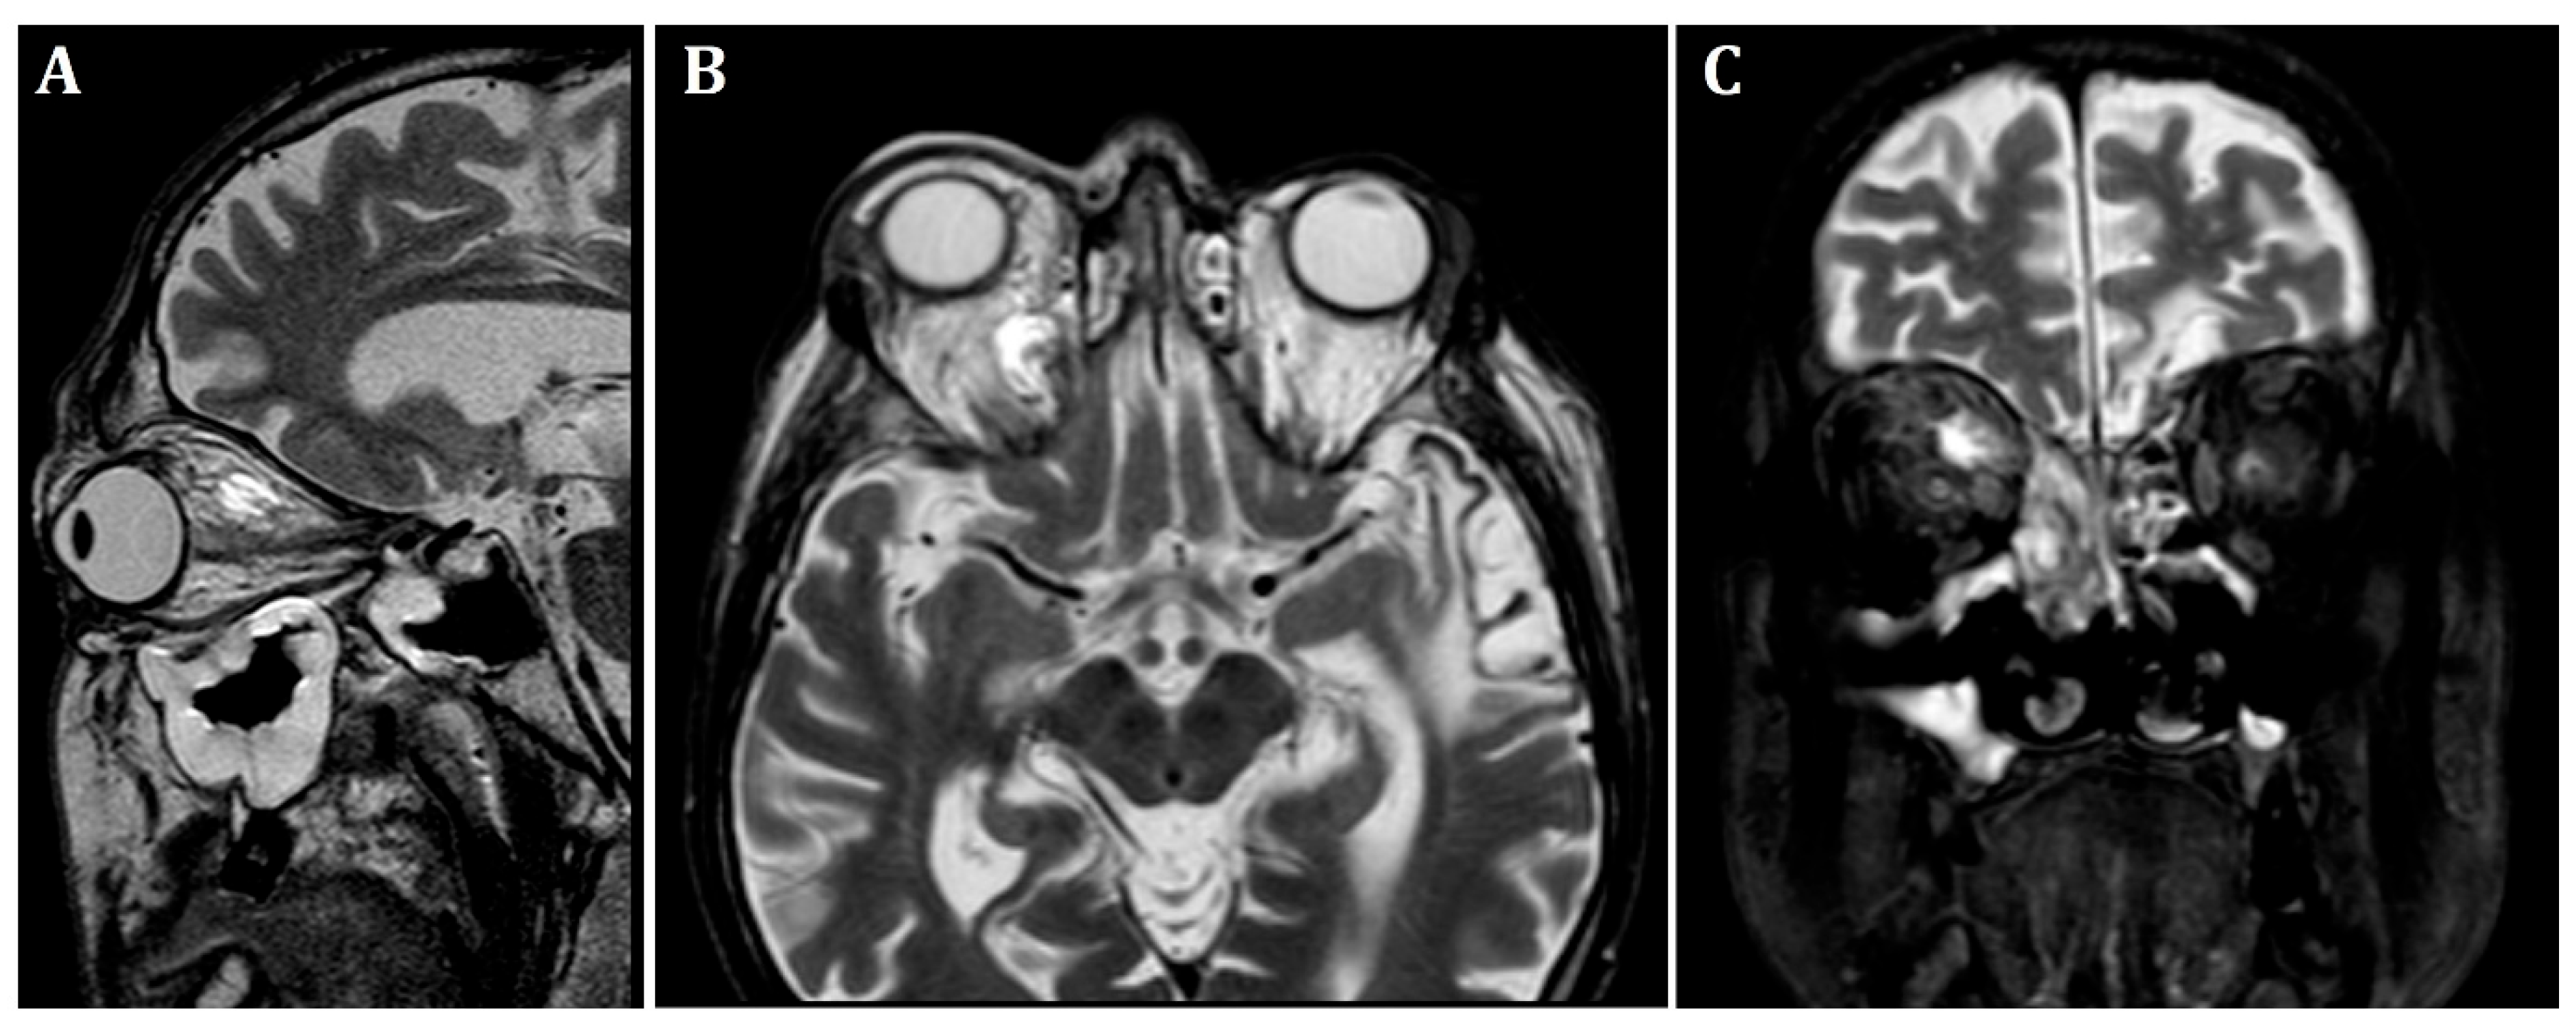

At the patient’s initial presentation at the Otolaryngology Department of the secondary hospital, the magnetic resonance imaging (MRI) of orbits revealed infiltration of the right frontal, ethmoid and maxillary sinuses, extension into the right orbit’s soft tissue and extraocular muscles with optic nerve invasion (Figure 1). The ophthalmological examination revealed central retinal artery occlusion. The treatment with ceftriaxone, vancomycin, fluconazole, mannitol and methylprednisolone was initiated. Due to clinical suspicion of mucormycosis, the patient was transferred to the University Hospital in Cracow.

Figure 1. Initial pre-operative magnetic resonance imaging. T2-weighted MRI scans of the orbits. (A)—sagittal, (B)—frontal, (C)—transverse planes. Visible infiltration of extraocular muscles and optic nerve. Inflammatory opacifications in ethmoid cells and maxillary sinus, extending into the orbital adipose tissue and extraocular muscles, causing osseous destruction of ethmoid cells.